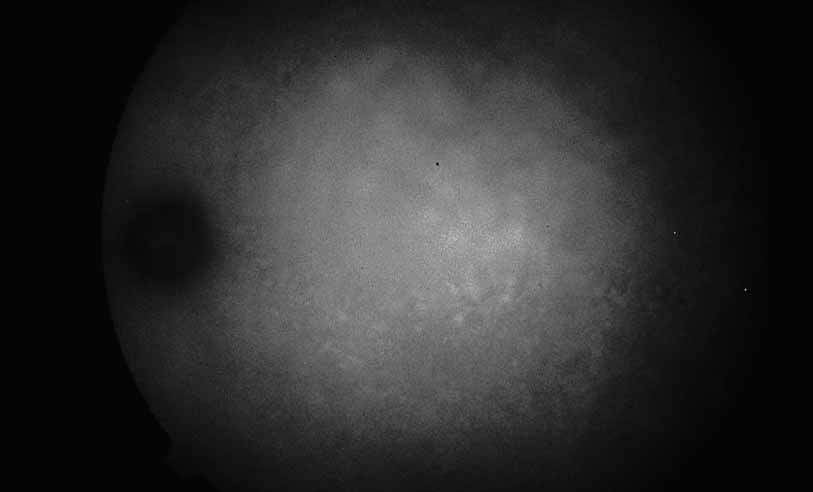

In addition to exudative detachment of the neurosensory retina and papillitis, patients with Vogt-Koyanagi-Harada disease as well as sympathetic ophthalmia may also develop serous detachment of the retinal pigment epithelium. This differs from the usual form of retinal pigment epithelium detachment that occurs in age-related macular degeneration by the absence of adjacent soft drusen and the presence of multiple pinpoint leak sites and disc staining characteristic of Vogt-Koyanagi-Harada disease (see Figs. 30, 31, 32, 33, and 34) and sympathetic ophthalmia (see Figs. 35 and 36).41–46 In cases of Vogt-Koyanagi-Harada disease with serous retinal detachment or detachment of the retinal pigment epithelium, some authors have reported hyperfluorescence of the large choroidal vessels in early stages of the angiogram, followed by dye leakage in the late phase of the study, whereas others report leakage from the choroidal vessels throughout the study (see Figs. 33 and 34).11,12

Fig. 30 Vogt-Koyanagi-Harada syndrome. Color photograph. A young woman presented with 1-week history of blurred vision and metamorphopsia. Other findings included vitiligo and tinnitus. Examination revealed a serous macular detachment.

Fig. 31 Vogt-Koyanagi-Harada syndrome. Fluorescein angiography shows multiple spots of deep hyperflourescence within the serous detachment

Fig. 32 Vogt-Koyanagi-Harada syndrome. Later frames of the fluorescein show increased leakage with pooling.